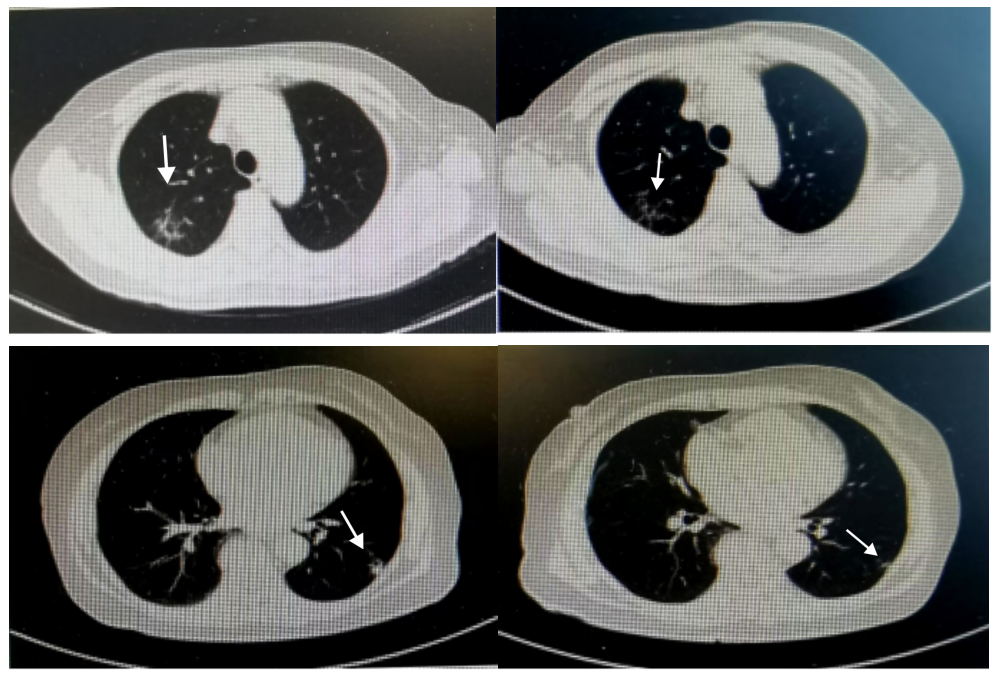

Main examination: Enhanced CT of the chest and abdomen indicated: solid lesions in the left lower lobe and right upper lobe increased compared to before, likely metastatic.

Started treatment with Vadimezan 120mg + Toripalimab 240mg, every two weeks, with follow-up after six cycles.

Significant reduction in lung metastatic lesions. Follow-up ultrasound: outpatient examination of superficial color Doppler ultrasound indicated: examination of the mass in the right flank: a low echo of 1.7×1.0x1.2cm visible in the fat layer, with clear boundaries and regular shape. Considered as metastatic lesions.